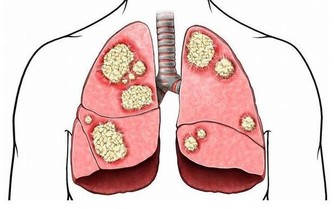

人之所以疼痛部位、 患的疾病不同,就是因為不同的地方被瘀血堵塞。瘀血還和哮喘、牛皮癬、抑鬱類疾病、婦科疾病的關聯很大;水濕和脾胃腎臟的功能、肌肉類疾病、黃斑病等關聯很大;食瘀和心血管疾病、膽囊胰臟疾病、瘡疔癰膿類疾病的關聯很大。

前人云:“癌瘤者,非陰陽正氣所結,乃五臟瘀血濁氣痰滯而成。毒和瘀是人體內的垃圾,時刻都會產生,身體一系列瘀堵,會使臟腑功能失調,氣血不和,濁邪積聚,漸漸積累就變成癌。